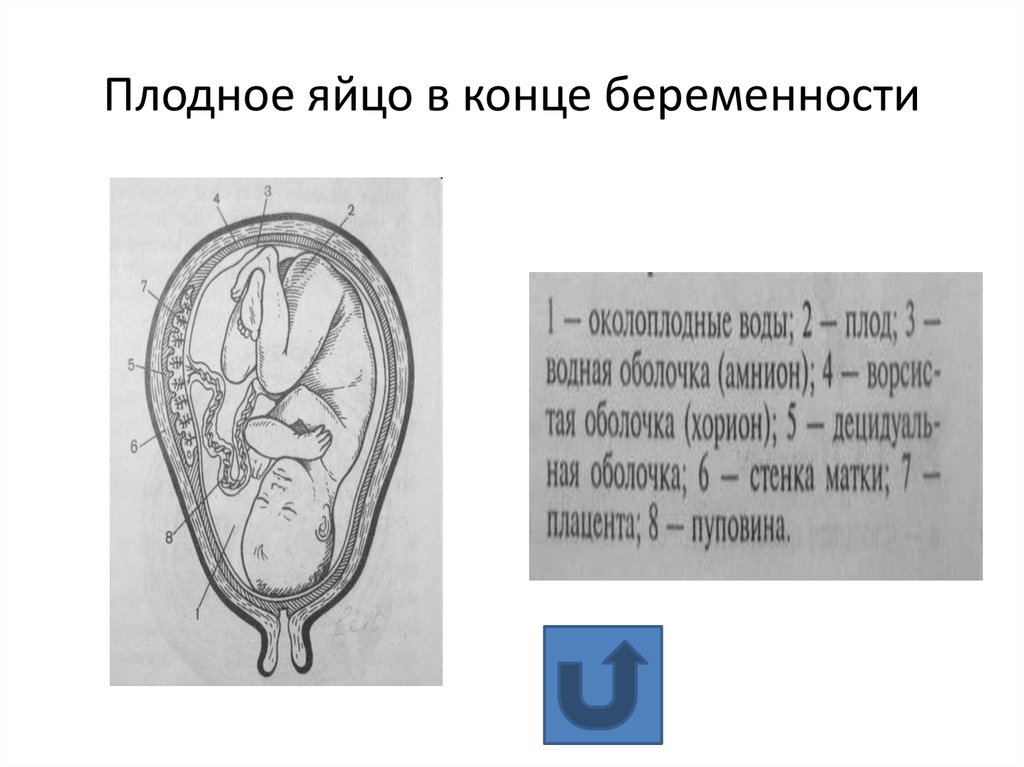

Околоплодный пузырь и плацента: структура и функции